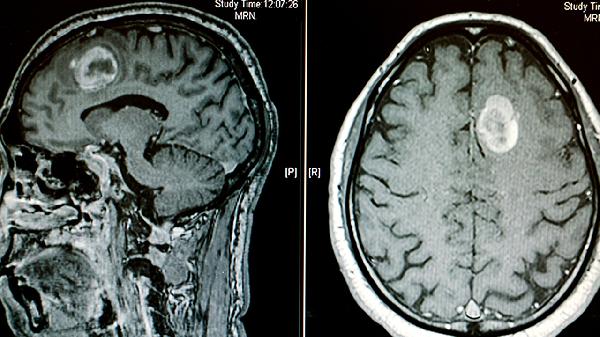

轻度闭合性颅脑损伤的患者通常会出现短暂的意识丧失,时间一般不超过半小时,可能伴随头痛、头晕、恶心、呕吐等表现。神经系统检查通常没有明显异常,而通过头颅CT或MRI等影像学手段,可能会发现正常或者仅有轻微的变化。这类损伤多由跌倒、车祸、运动时受伤等原因引起,脑部受损情况不严重,没有出现大出血或严重的脑挫裂伤。治疗上以休息和对症处理为主,医生可能会推荐使用布洛芬缓释胶囊、对乙酰氨基酚片等药物来缓解头痛,或者用甲氧氯普胺片控制呕吐。多数患者在1到2周内症状会逐渐减轻,预后较好。

不过,也有少数轻度闭合性颅脑损伤患者可能出现症状持续不减或加重的情况,比如头痛超过两周、频繁呕吐、意识状态变化等,这可能与脑震荡后综合征或慢性硬膜下血肿等并发症有关。对于这些患者,医生可能会安排进一步的检查,如头颅MRI或脑电图,根据结果调整治疗计划,必要时可能需要神经外科介入。即使症状持续,大多数人在3到6个月后也会逐步好转。